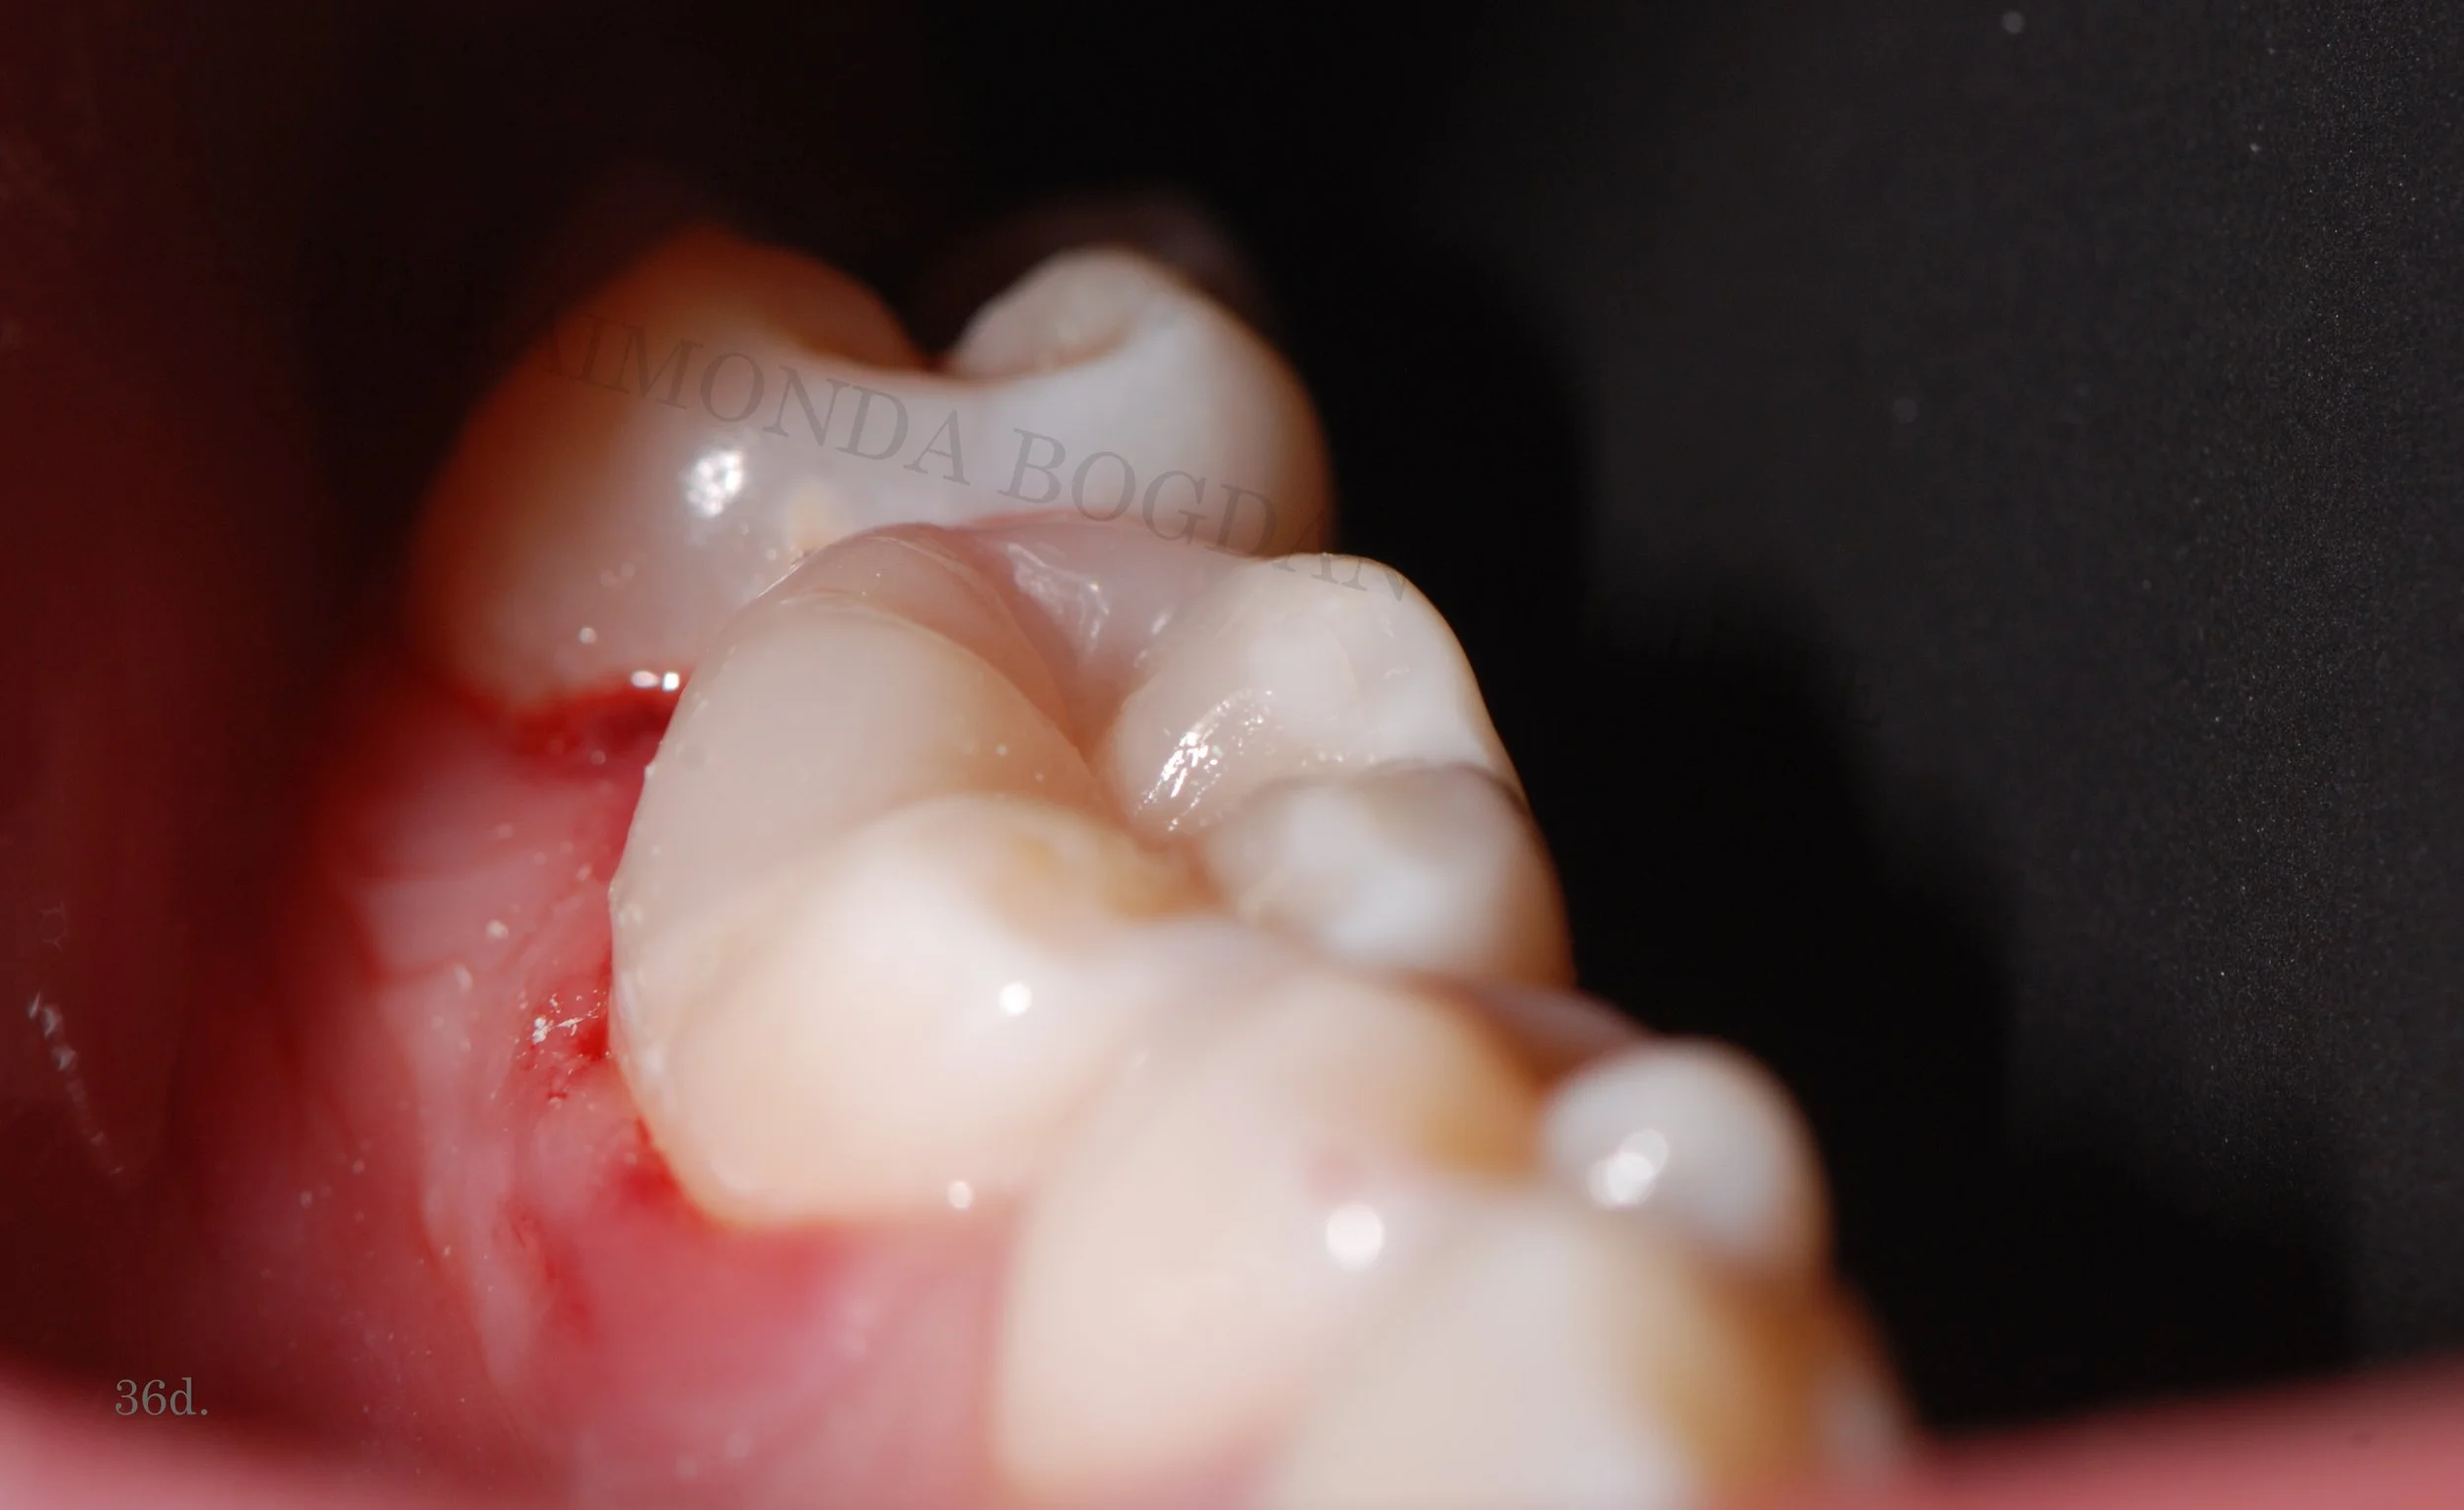

Functional Restorations

These are dental reconstructions that precisely rebuild lost dental tissue and returns full functionality for the teeth.

What is a functional restoration?

A functional restoration is any small or big dental reconstruction that re-creates lost dental anatomy and function. Every single cusp, ridge or groove on the surface of the tooth has a particular function and participates in chewing. Wrong reconstruction can lead to different negative consequences and even affect your overall health - poor mastication, tooth fracture, tooth pain, malposition of teeth, gingivitis, periodontitis, bone loss, headaches and many more.

Better than before

Correctly performed functional restoration following strict protocols guarantees long-lasting excellent results for plenty of years avoiding any of those negative oral health issues, strengthening your teeth and improving your mastication.

All our fillings from the smallest to the biggest one are performed in this way.